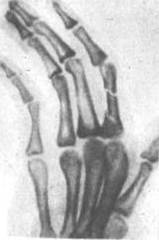

Кисть —

лучезапястного сустава, расположенная на 1 см выше линии между шиловидными отростками лучевой и локтевой костей (7, с.67).

Рисунок

1- Строение кисти

В кисти

различают ладонную и тыльную поверхности и три части: запястье, пясть и пальцы.